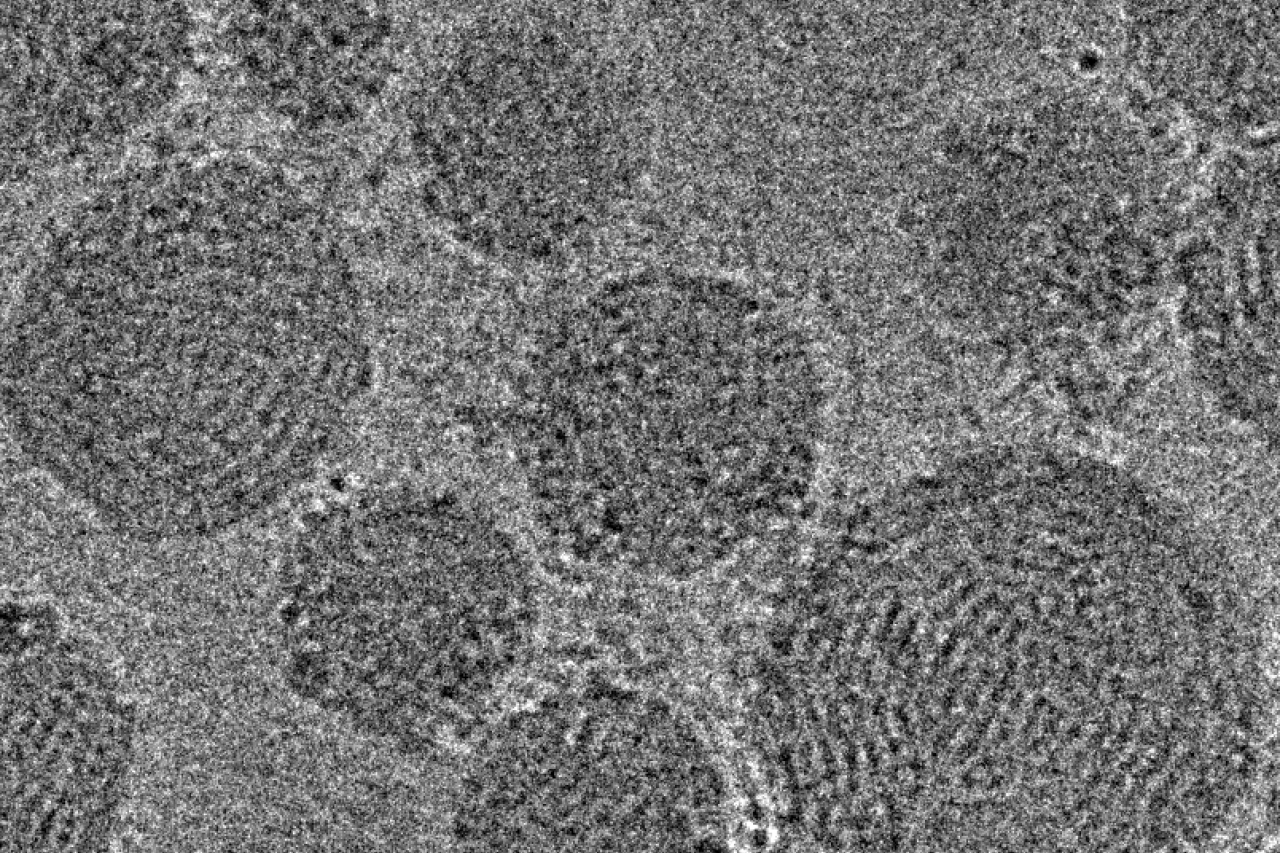

Representative cryo-TEM images of lipid nanoparticles carrying CRISPR/Cas9 gene editing components, including a Cas9-encoding mRNA, guide RNA, and a linear double stranded DNA template of the CFTR gene.

Representative cryo-TEM images of lipid nanoparticles carrying CRISPR/Cas9 gene editing components, including a Cas9-encoding mRNA, guide RNA, and a linear double stranded DNA template of the CFTR gene. | Credit: Ruth Foley and Willus Fisher, Jonas Lab